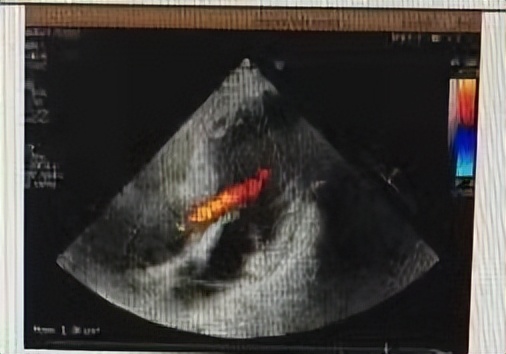

影像学结果中心脏超声检查提示:主动脉及升主动脉增宽,室间隔增厚,主动脉瓣轻度返流,二尖瓣轻度反流,左室收缩功能正常,舒张功能减弱。为了鉴别诊断,还进一步进行了腹部CT检查,结果提示左侧肾上腺内、外侧枝根部增粗,考虑肾上腺增生、右肾小结石。